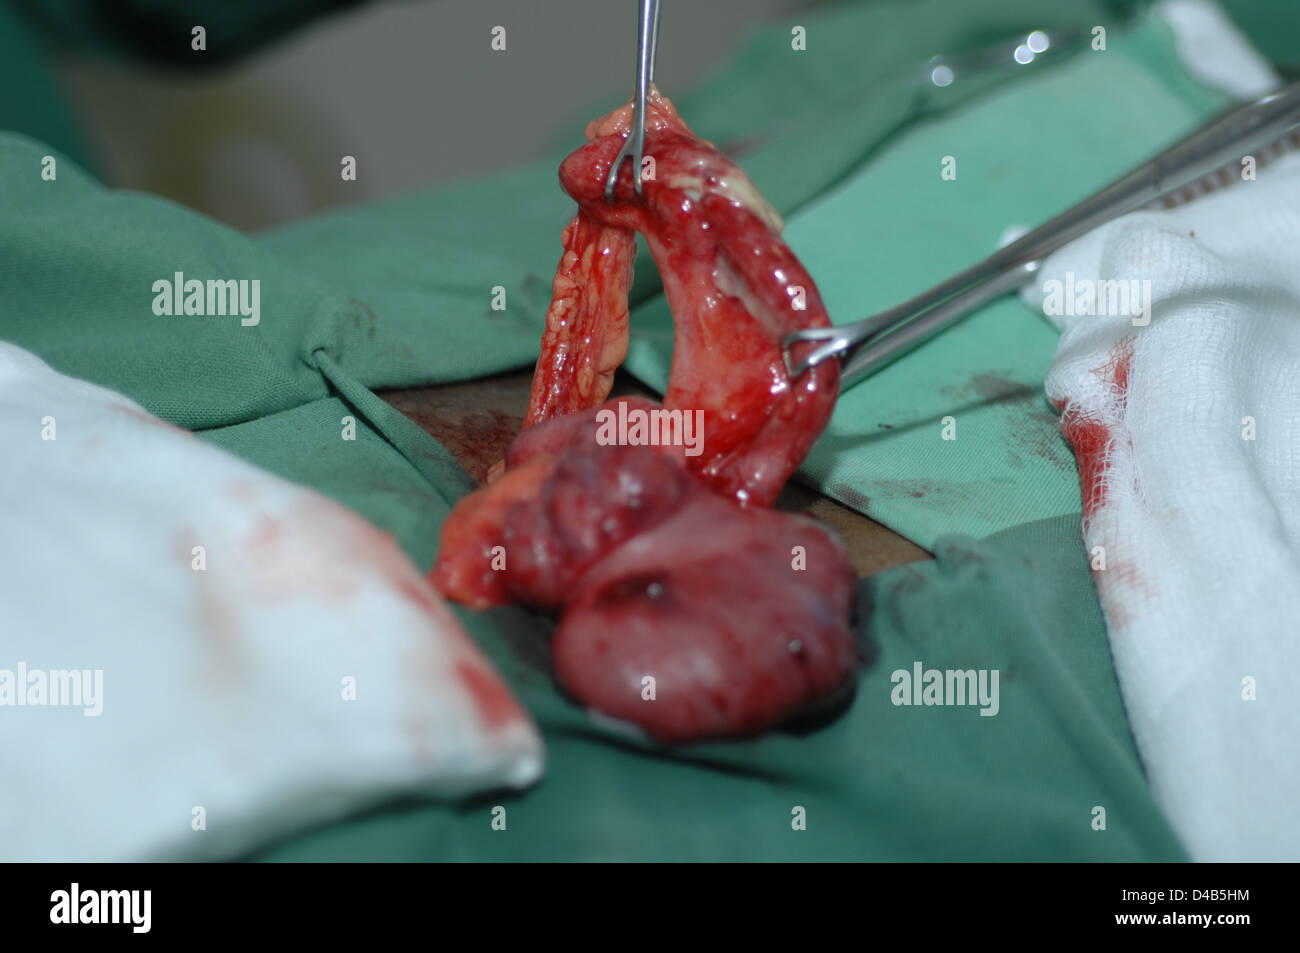

RMD4B5HM–Der Chirurg untersucht Mesoappendix Blut Versorgung Anhang zu beurteilen. Arterien werden vor dem Anhang entfernen ligiert